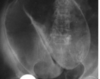

ENUNCIADO DEMOSTRA FRATURA PÉLVICA , COM DESLOCAMENTO DA PRÓSTATA AO TOQUE.

1.CONDUTA –> FIXAÇÃO EXTERNA DA PELVE .

O EXAME DEMONSTRADO É :

1.URETROCISTOGRAFIA RETRÓGRADA ( CONSIDERAR CONTEXTO DO TRAUMA )

2.DEMONSTRA LESÃO DE URETRA .

LEMBRANDO QUE NESSE CASO , NÃO PODEMOS FAZER CATETERIZAÇÃO VESICAL .

* SE A URETROCISTOGRAFIA ESTIVESSE NORMAL DEVERÍAMOS REALIZAR CISTOGRAFIA.